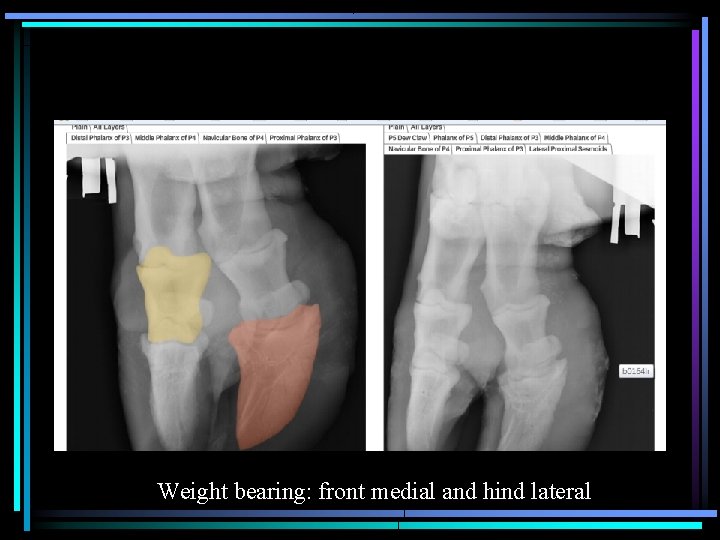

Weight bearing: front medial and hind lateral